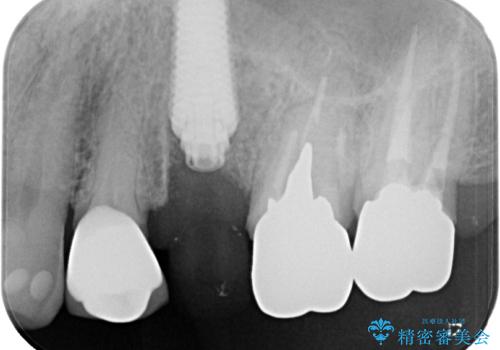

抜歯即時埋入後にはずっと気になっていた排膿が消え、痛みも腫れも特になく、3ヶ月という短期間で無事に治療を終えることができました。

破折した奥歯 抜歯即時埋入インプラントによる補綴治療